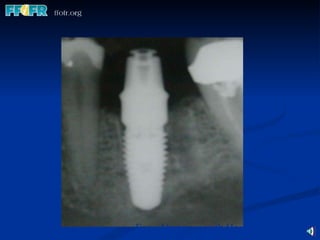

Fixture Original Threaded Fixture External hex headed  Original Brånemark had only a machined surface. Newer versions have an “enhanced” surface. Lengths 7-20 mm in regular platform  Widths / Platforms: Narrow:  3.3mm Regular:  3.75 and 4.0 mm Wide:  5mm

Fixture Original ThreadedFixture External hex headed Original Brånemark had only a machined surface. Newer versions have an “enhanced” surface. Lengths 7-20 mm in regular platform Widths / Platforms: Narrow: 3.3mm Regular: 3.75 and 4.0 mm Wide: 5mm